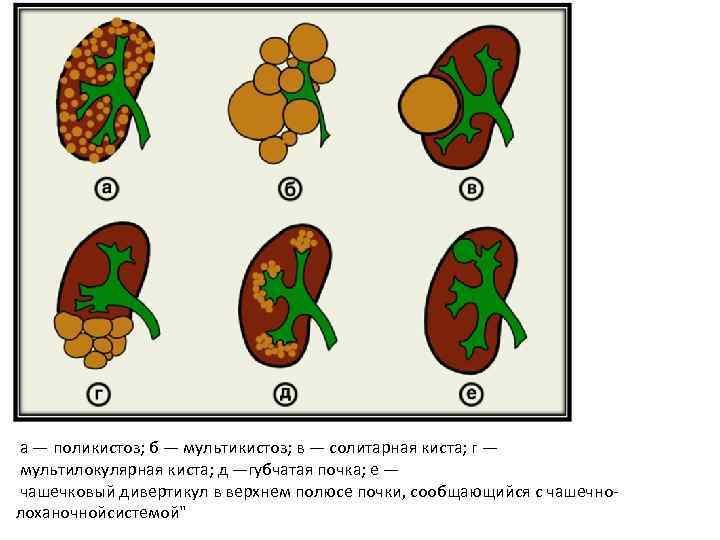

Аномалии структуры почек Дисплазия почки. Мультикистоз почки. Поликистоз почек: поликистоз взрослых; поликистоз детского возраста. Солитарные кисты почек: простая; дермоидная.

Аномалии структуры почек Дисплазия почки. Мультикистоз почки. Поликистоз почек: поликистоз взрослых; поликистоз детского возраста. Солитарные кисты почек: простая; дермоидная.

а — поликистоз; б — мультикистоз; в — солитарная киста; г — мультилокулярная киста; д —губчатая почка; е — чашечковый дивертикул в верхнем полюсе почки, сообщающийся с чашечнолоханочнойсистемой"

а — поликистоз; б — мультикистоз; в — солитарная киста; г — мультилокулярная киста; д —губчатая почка; е — чашечковый дивертикул в верхнем полюсе почки, сообщающийся с чашечнолоханочнойсистемой"